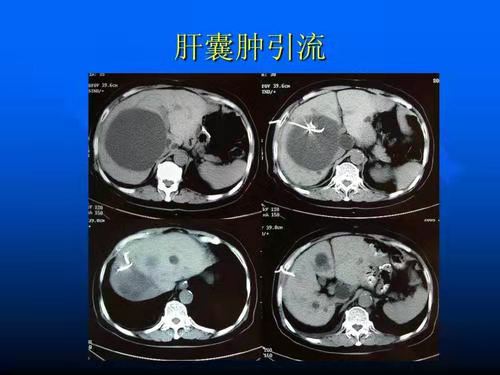

图片 1

3)对于并发感染、囊内出血、囊液有胆汁者可行开窗术后置管引流